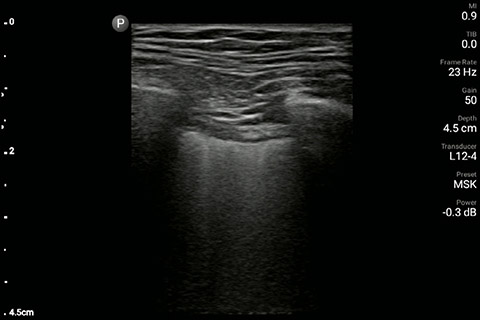

The patient had reduced LV systolic function without new or severe valvular pathology, a dilated, non-collapsing IVC, and diffuse B lines (left greater than right) on lung ultrasound imaging.

Lung image of the left chest

M-mode demonstrating lung sliding

In the interim, while awaiting laboratory results and chest X-ray imaging, POCUS with a three-point exam (F-TTE, IVC collapsibility, and lung ultrasound) was used for bedside evaluation of the etiology of the patient’s dyspnea. Within minutes, and with the additive information from the combined cardiac, subcostal IVC, and lung ultrasound imaging, the patient was diagnosed with acute on chronic congestive heart failure and flash pulmonary edema as the cause of his respiratory distress and hypoxia.